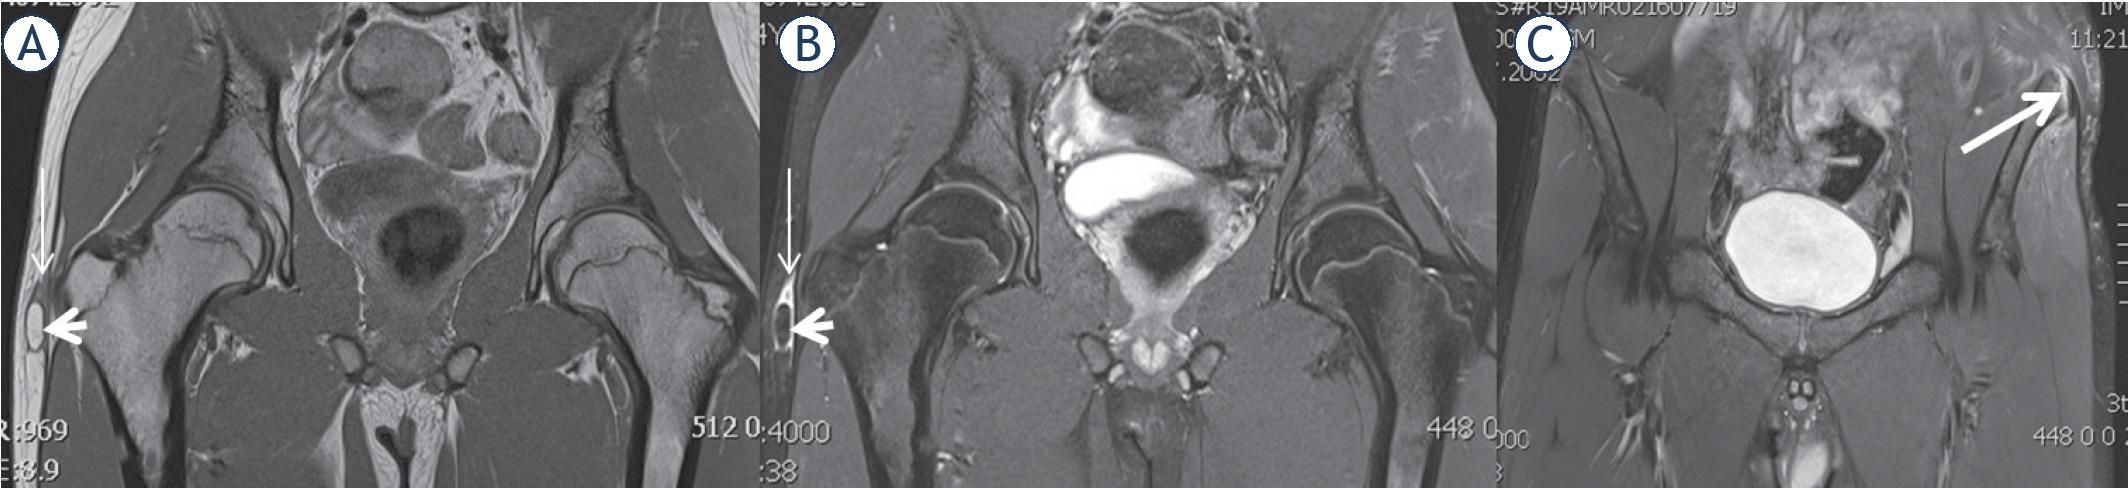

Figure 4